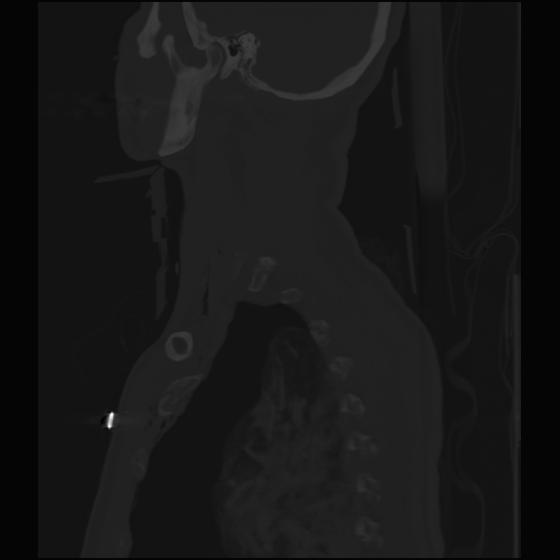

24 ANGIO,CE,Sag-MIP,5.000,ANGIO,Sag-MIP,